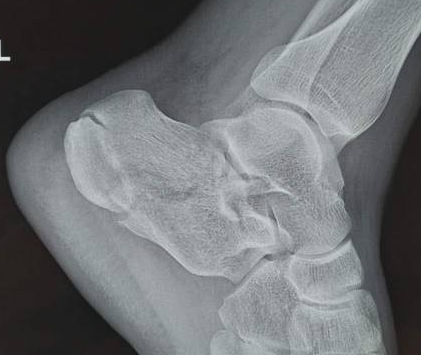

跟腱炎一般是由慢性、反复的跟腱劳损,或是有外伤诱发引起的,也有不少是骨质增生、骨刺等诱发引起的。跟腱炎属于软组织病变,尽管想要完全防止跟腱炎的发生是不可能的,但是可以采取一些措施来降低它的风险。